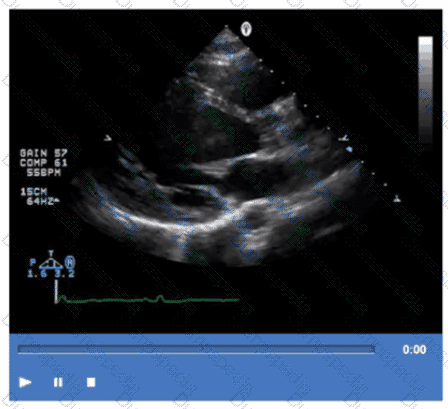

Which diagnosis is most likely confirmed by echocardiography in a 65-year-old female presenting with new onset chest pain associated with ST segment elevation on the electrocardiogram and angiographically normal coronary artenes?